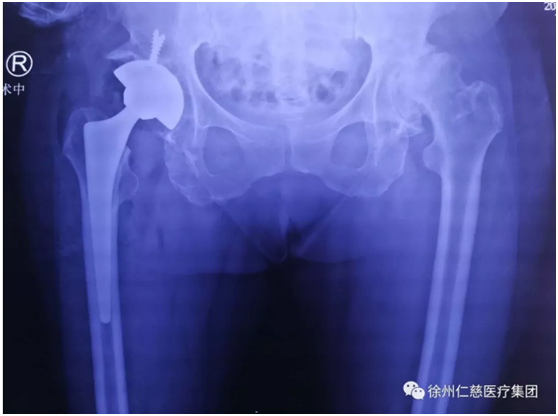

昨天,郝亮技術(shù)團(tuán)隊(duì)給李師傅施行了全髖關(guān)節(jié)置換手術(shù),手術(shù)很順利,如今,李師傅正在關(guān)節(jié)病區(qū)康復(fù)。

(術(shù)后)